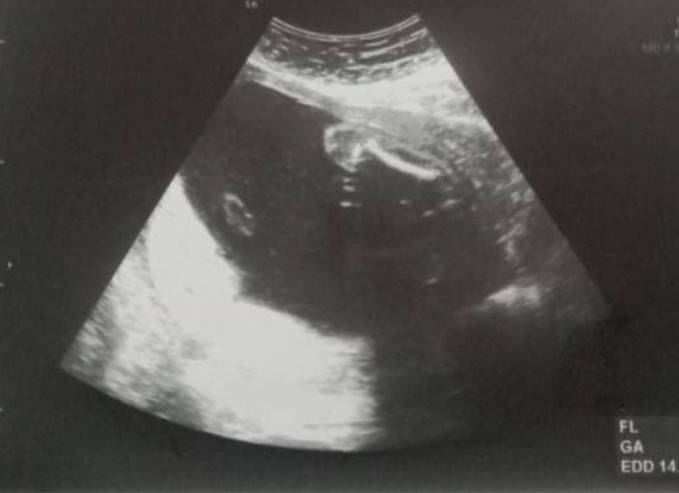

ช่วยดูให้หน่อยได้ไหมคะคะ..ว่าได้ผู้ชายหรือผู้หญิง